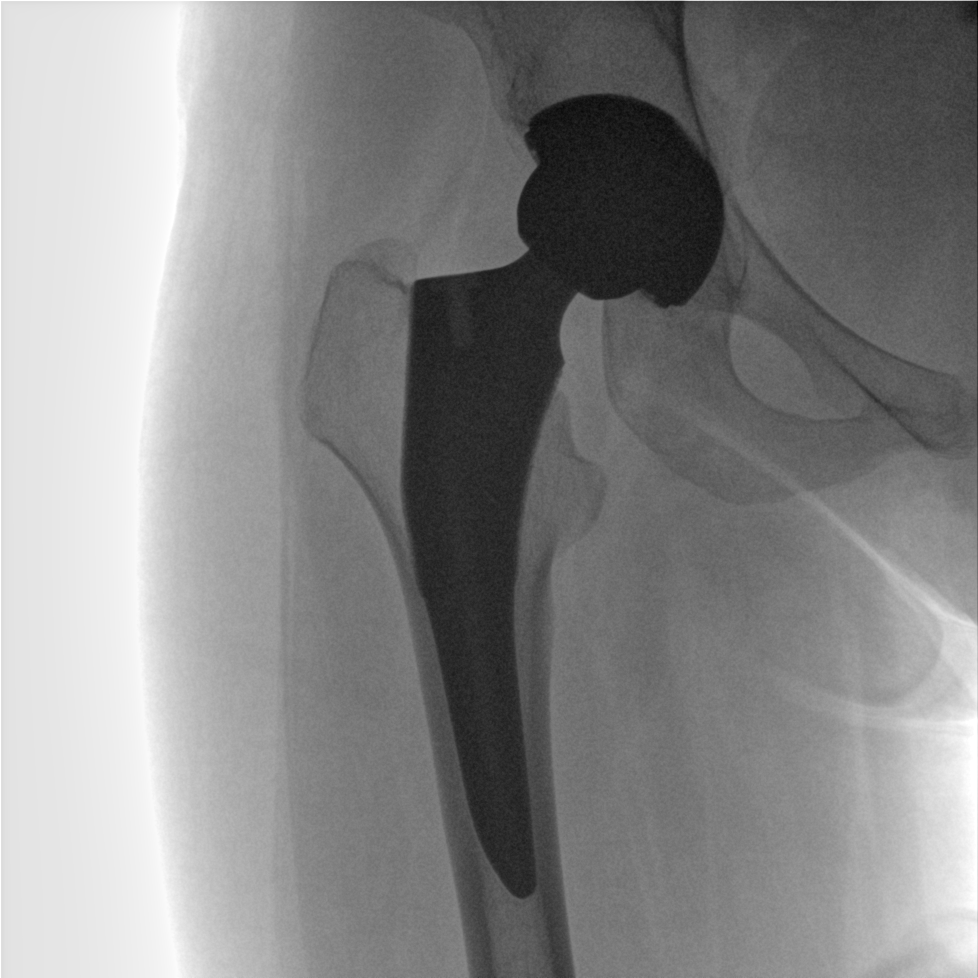

提供更大的術(shù)中三維成像視野,采集更多圖像信息,可一次拍全全段頸椎、全段腰椎、七節(jié)胸椎、雙側(cè)骶髂關(guān)節(jié)、股骨頭及單側(cè)盆骨。